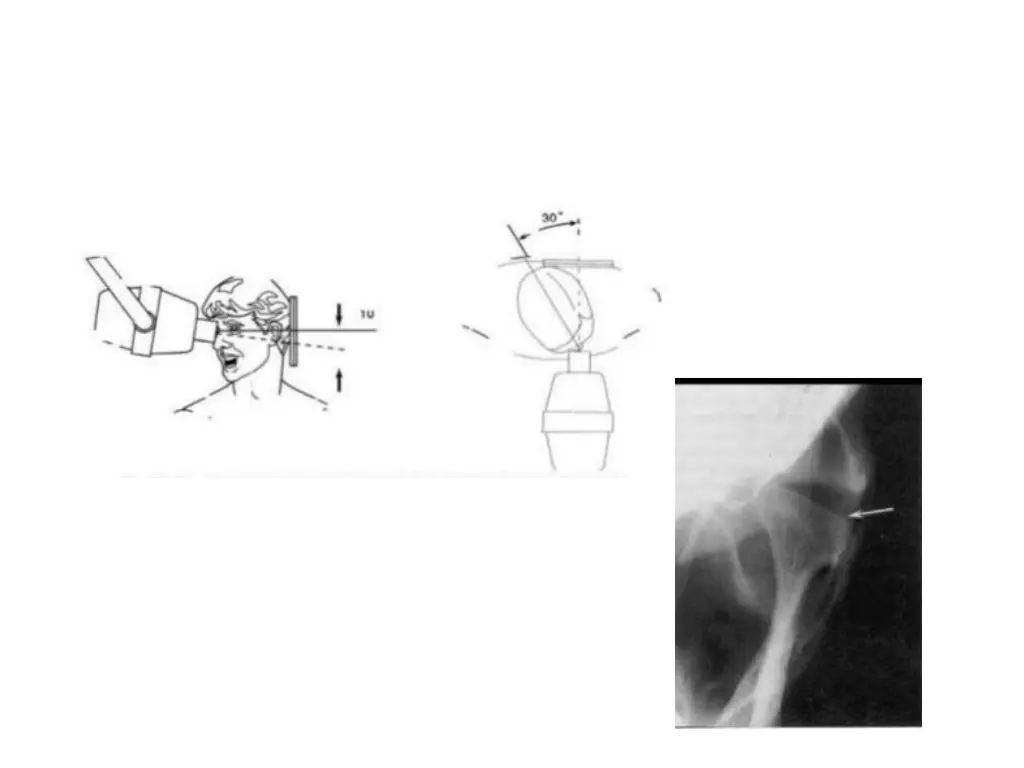

Transcranial projection It provides a saggital view of lateral aspects of condyle and temporal component Pt is positioned in a cephalostat and x ray beam is directed downward from the opposite side, through the cranium and above the petrous ridge of temporal bone, at a 25 degree angle centered through the joint and 20 degree anterior angle may be used Film cassatte is placed on side of concern It includes in closed and maximal open positions

Coz of positive beam angulation, central and medial aspects of joint are projected inferiorly and only lateral joint contours are visible in this projection Ipsilateral petrous ridge is often supermposed over condylar neck and so condylar head, temporal component and joint space is distorted. So horizontal beam angle be individualized to each pt Indications: gross osseous changes on lateral aspect of joint, displaced condylar fractures, and range of motion

Transpharyngeal projection (Pharma) Provides a saggital view of medial pole of condyle Beam is directed superiorly at -5 degrees through the sigmoid notch of opposite side and 7 to 8 degrees from anterior Film cassatte is palced on side being imaged Pt opens the mouth maximally to avoid superimposition of condyle on temporal component Coz of negative angulation, this view depicts medial aspect of condyle Indications: for visualizing erosive changes of condyle rather than subtle changes